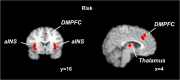

In our everyday life, we often have to make decisions with risky consequences, such as choosing a restaurant for dinner or choosing a form of retirement saving. To date, however, little is known about how the brain processes risk. Recent conceptualizations of risky decision making highlight that it is generally associated with emotions but do not specify how emotions are implicated in risk processing. Moreover, little is known about risk processing in non-choice situations and how potential losses influence risk processing. Here we used quantitative meta-analyses of functional magnetic resonance imaging experiments on risk processing in the brain to investigate (1) how risk processing is influenced by emotions, (2) how it differs between choice and non-choice situations, and (3) how it changes when losses are possible. By showing that, over a range of experiments and paradigms, risk is consistently represented in the anterior insula, a brain region known to process aversive emotions such as anxiety, disappointment, or regret, we provide evidence that risk processing is influenced by emotions. Furthermore, our results show risk-related activity in the dorsolateral prefrontal cortex and the parietal cortex in choice situations but not in situations in which no choice is involved or a choice has already been made. The anterior insula was predominantly active in the presence of potential losses, indicating that potential losses modulate risk processing.